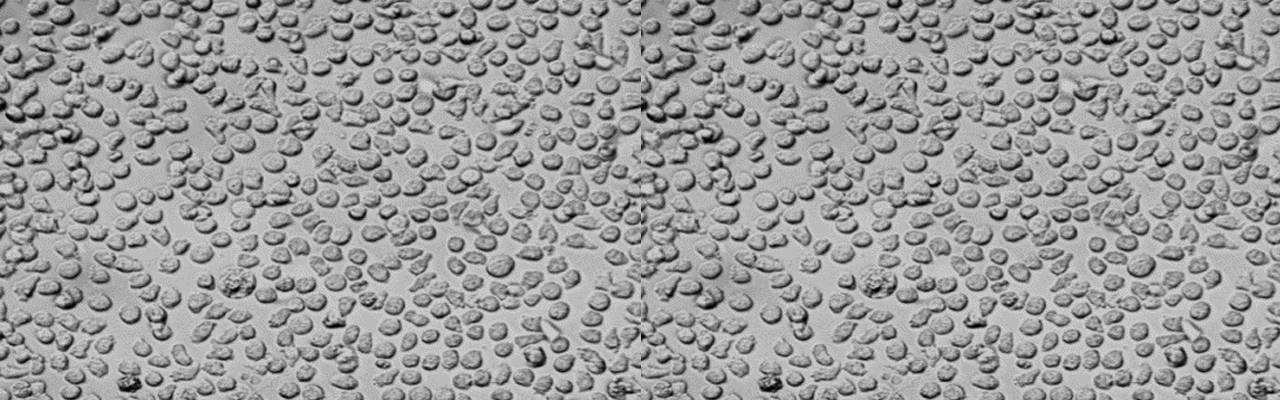

| 细胞全名 | MV-4-11(人髓性单核细胞白血病细胞) |

| 生长特性: | 悬浮 |

背景资料:MV-4-11细胞系由Rovera课题组建立,来源于一名患有人双表型髓性单核细胞白血病(biphenotypic B myelomonocytic leukemia)的10岁男孩的外周血。Interleukin (IL)-3可以独立地支持该细胞长期生长,使用10%FBS培养时则不需要额外添加IL-3。但是,在IL-3和生长因子Granulocyte/Macrophage Colony-Stimulating Factor (GM-CSF)均处于低浓度的情况下,IL-3会抑制MV-4-11细胞的增殖。生长因子Granulocyte Colony Stimulating Factor(G-CSF)会协同GM-CSF促进MV-4-11细胞的增殖,而单独的G-CSF会短暂刺激该细胞系。据文献[PubMed: 3500218]报道,间接免疫荧光法检测髓性单核细胞抗原CD15,超过96%的该细胞为阳性,40~96%为单核细胞抗原CD4阳性,4-11%为单核细胞抗原CD10阳性。每个批次均通过本库支原体检测,结果为阴性。